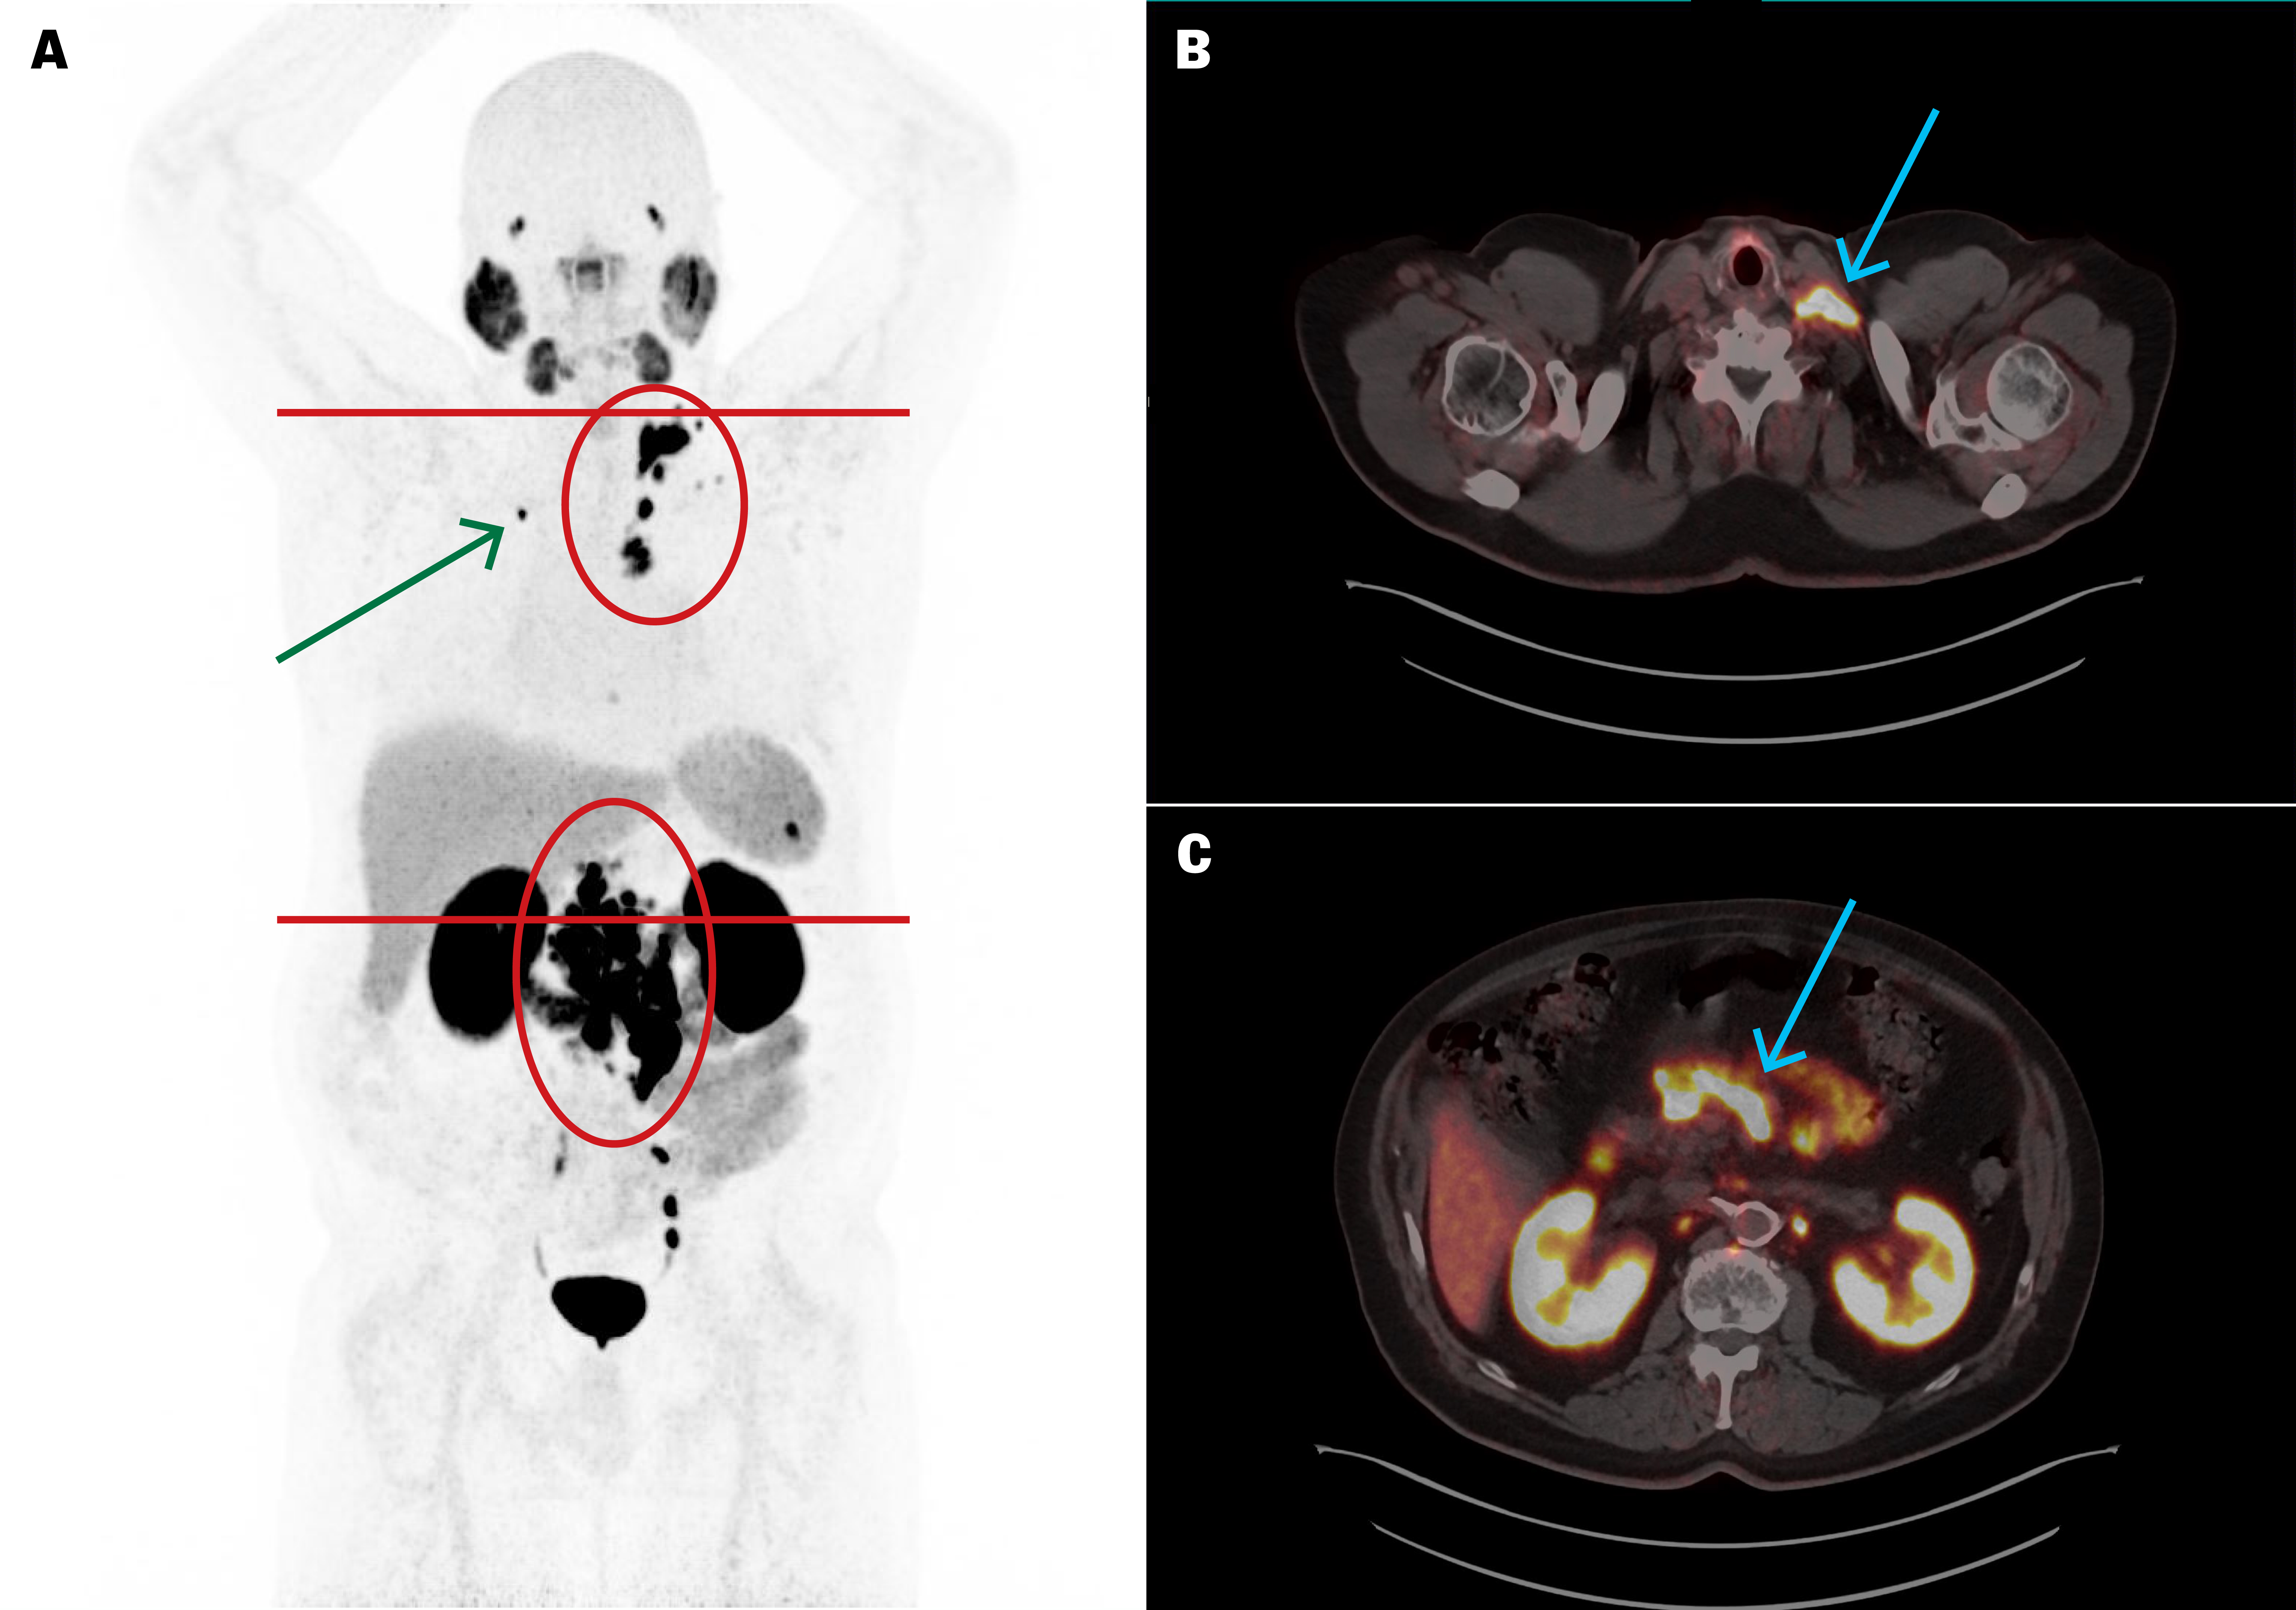

Fem uker etter femte behandling var p-PSA 1,8 µg/L. [⁶⁸Ga]PSMA-11 PET/CT viste betydelig størrelsesreduksjon av metastasene (figur 2), der den største (mållesjon) hadde redusert diameter fra 10 til 4 mm. Ut over nedsatt matlyst og forstoppelse ble behandlingen godt tolerert uten affeksjon av nyre-, spyttkjertel- eller benmargsfunksjon.

Syv måneder etter femte behandling hadde p-PSA steget til 14,3 µg/L og [⁶⁸Ga]PSMA-11 PET/CT viste tilkomne små skjelettmetastaser med høyt opptak, mens lymfeknutemetastasene var uendrete. Behandlingen ga altså god, men forbigående effekt på metastasene.